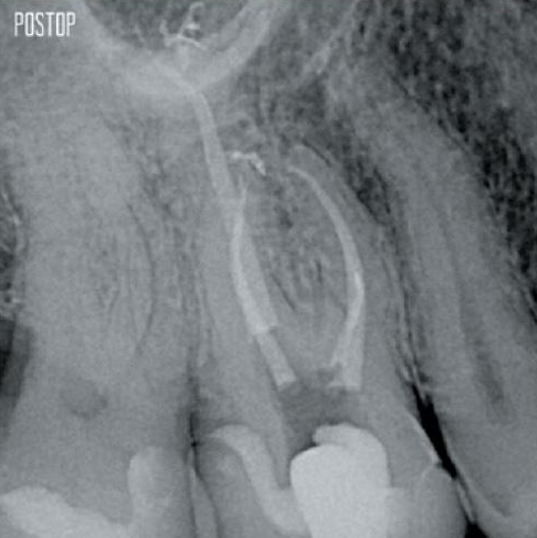

Foto's met dank aan dr. Ahmed Salman

Meer dentine behouden. Goede vormgeving, irrigatie en obturatie verzekerd.